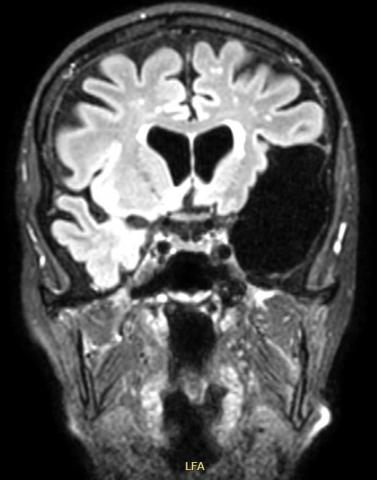

MR-skanningsbillede af stor arachnoideacyste i venstre temporal­region.